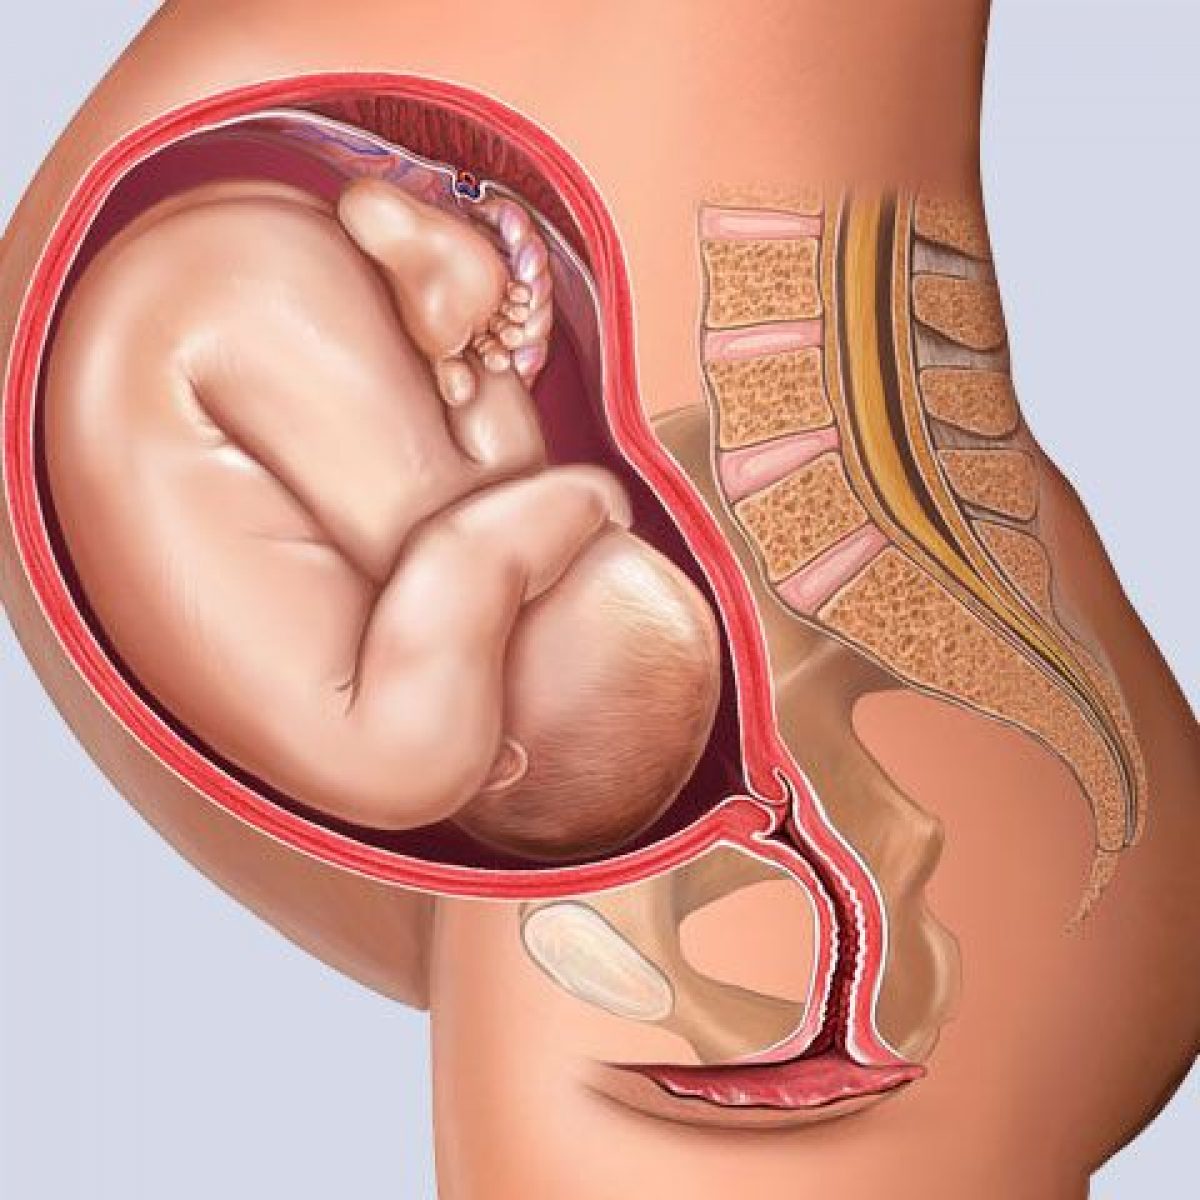

Плод 39 Недель Фото

Плод 39 Недель Фото 100 фото